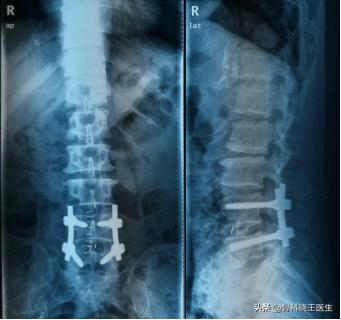

手术可以选择单纯髓核摘除或者同时进行椎间融合内固定等方法,每一种术式都有其优势与不足,专业的骨科医生会根据病情不同,选择最合适的手术方案。

单纯髓核摘除创伤小,但间盘组织留有残余,有可能复发

椎间融合内固定相同节段不会复发,但费用较高,内固定可能需要二次取出